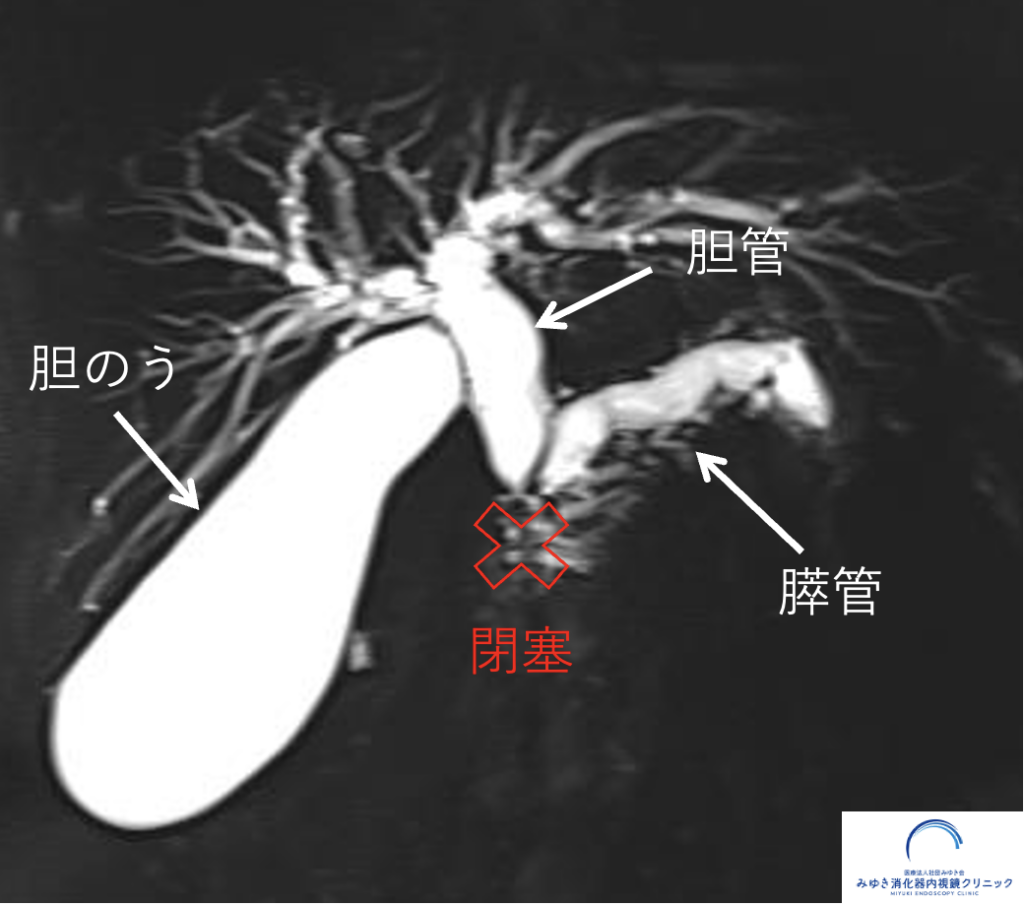

膵管とは、膵臓の中を通る管で、消化液(膵液)を流す役割があります。

通常は細い管(2mm程度)ですが、何らかの原因で太くなることがあります。

① 膵がん

がんにより膵管が詰まる(狭窄)ことで、上流が拡張します

膵管拡張は、このような原因によって起こります。では実際の症例を見てみましょう。

▶️ この症例の詳細についてはこちら